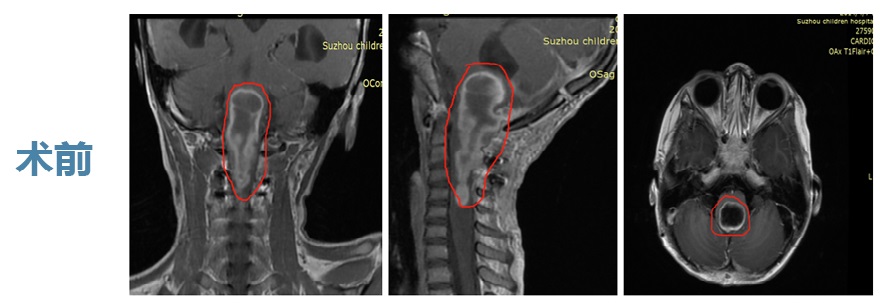

MR平掃結(jié)果提示:腦干延髓區(qū)占位性病變。

之后,完善顱腦MR增強(qiáng)掃描提示:腦干延髓區(qū)有2.8*2.7*7.5cm較大占位,病灶囊性部分突向四腦室,雙側(cè)側(cè)腦室、三、四腦室擴(kuò)張,考慮室管膜瘤伴腦積水、間質(zhì)性腦水腫可能。

腦膠質(zhì)瘤患者圖片——寶寶膠質(zhì)瘤能治愈嗎

寶寶膠質(zhì)瘤能治愈嗎

預(yù)后:腫瘤切除95%以上

經(jīng)巴特朗菲教授手術(shù)后,琦琦的腫瘤被切除95%以上,核磁影像幾乎看不到明顯的病變殘留。琦琦的神經(jīng)、肌肉功能得到大水平好轉(zhuǎn),手術(shù)結(jié)束后,琦琦的右側(cè)肢體活動(dòng)度、肌力已經(jīng)獲得了一些好轉(zhuǎn),右上肢即刻可抬高過(guò)肩。相對(duì)于術(shù)前的各種偏癱癥狀,這個(gè)結(jié)果讓琦琦父母驚喜萬(wàn)分,他們實(shí)在沒(méi)有想到效果如此明顯。

術(shù)后一天,琦琦在ICU病房留觀了一天,隨后轉(zhuǎn)入普通病房。巴教授拿著術(shù)前術(shù)后的影像對(duì)比來(lái)給爸爸媽媽做了詳細(xì)的解釋,包括手術(shù)入路、過(guò)程、切除情況,以及后續(xù)康復(fù)的評(píng)估和建議。術(shù)后一周,琦琦飲食由流食轉(zhuǎn)為常規(guī)飲食,精神狀態(tài)良好,右側(cè)肢體肌力進(jìn)一步恢復(fù)。